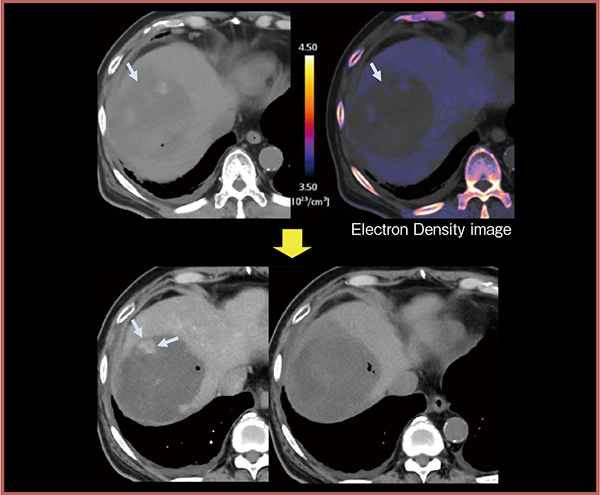

図4は,症例1(図2)と同一症例である。肝細胞がん破裂のため,ゼラチンスポンジを用いて緊急の肝動脈塞栓術(TAE)を行ったが,その後の経過観察にて残存病変の増大を認め,薬剤溶出性ビーズを用いたTACE(DEB-TACE)を施行した。1週間後に行った,合併症評価目的のCT検査にて電子密度画像を作成したところ,出血と思われる2つの高吸収領域の間にやや信号値の高い部分が見られ(図4↓),時間の経過とともに徐々に増大した。電子密度画像はDEB-TACE後の早期から,残存病変の予測や治療効果判定の指標になる可能性があると考える。

図4 電子密度画像によるDEB-TACE後の残存病変の予測